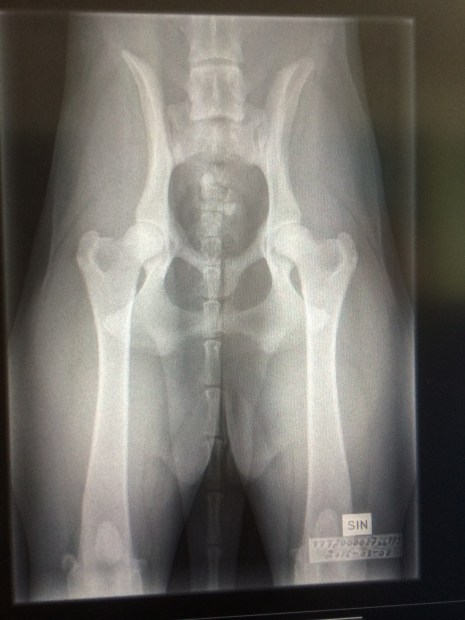

Idag har vi röntgat Mimmis armbågar för officiell avläsning ! Väntar med spänning på vad SKK säger. Passade på att kika på höfterna också !